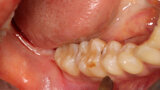

Fig. 17: The healed grafted ridge at 4.5 months following flap elevation demonstrating adequate width facial-palatally to allow implant placement.